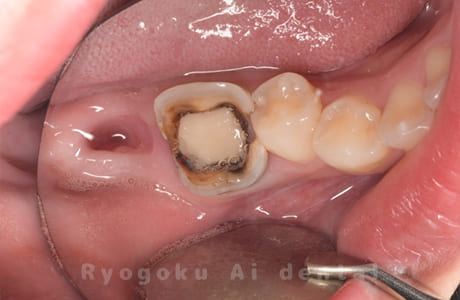

他院で右下の根の治療を行い、セラミックを被せる説明をされていたが、根の治療が終わらないため転院された患者さんです。隣の親知らずの抜歯の必要性と、根の治療を行なっている歯牙の予後が悪いため、移植治療を提案し、右下の親知らずの抜歯と同時に、右下の奥歯(7番)への移植治療を行いました。被せ物を行う必要もなく、順調に経過してます。